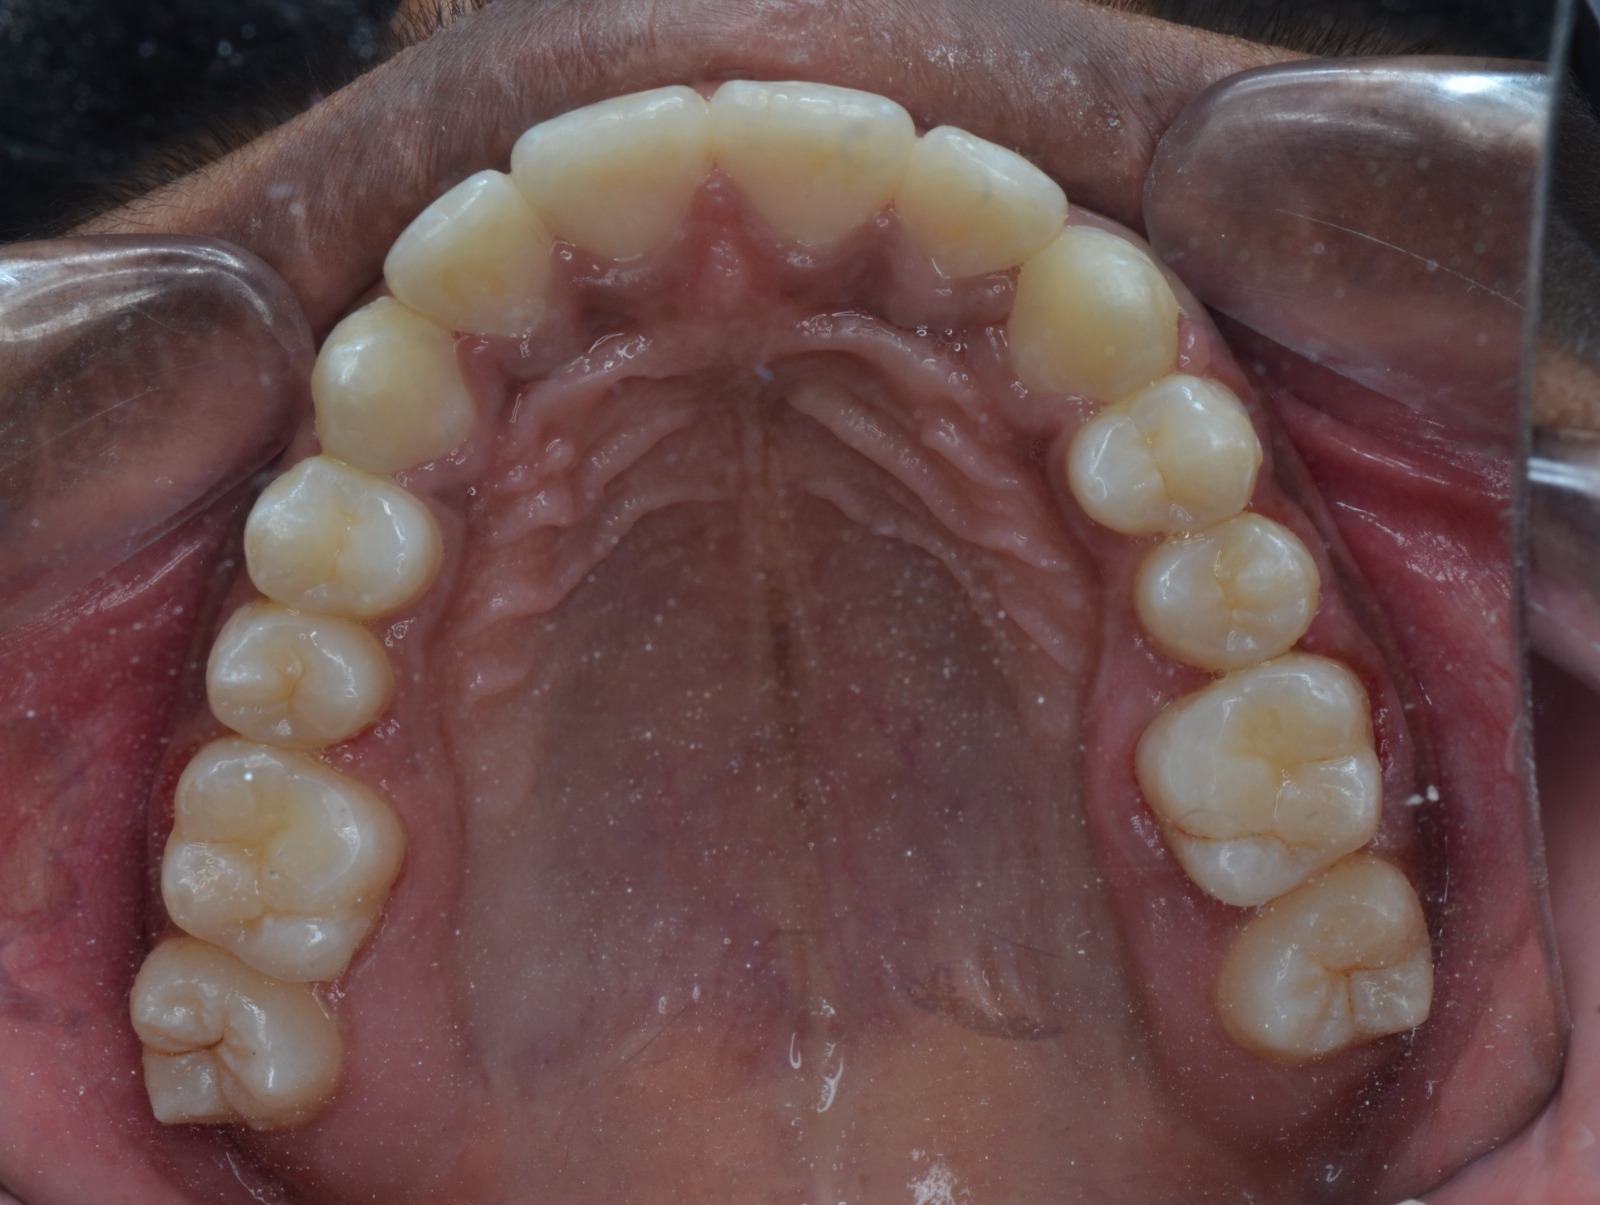

Sairam dental care located in Dharmapuri, with Leading Dentist In Oddapatti, is the Dental Hospital with exclusive root canal, Braces & Invisalign center. Led by renowned Drs Raghuraaman ( Periodontist) and Nivetha Raghuraaman ( Orthodontist) Sairam dental care offers gum treatment with expertise in laser, root canal treatment and digital smile correction with advanced technology aim to focus on aesthetics, comfort and precision. The clinic also specializes in Invisalign treatment, digital smile makeover, laser gum care, dental implants, root canal therapy, extractions and full-mouth rehabilitation blending compassionate care and clinical excellence.